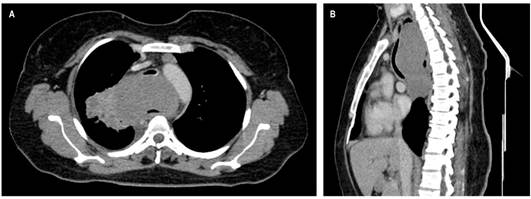

Se presenta el caso de una paciente femenina de 38 años con cuadro clínico consistente en disfagia de 1 año de evolución asociado con episodios ocasionales de hematemesis, por lo que se realizó una endoscopia de vías digestivas altas que evidenció una lesión endoluminal, friable e irregular que se localizó a 27 cm desde la arcada dentaria y de 12 cm de longitud, de la que se tomó una muestra para estudio histopatológico, que reportó una lesión benigna compatible con leiomioma. Sin embargo, se amplió el estudio con una TAC de tórax contrastada en la que se observó una masa tumoral a nivel del esófago cervical de 128 mm x 66 mm x 84 en diámetros L x AP x T, que se extiende hasta el esófago torácico transmural, exofítica, con realce homogéneo dependiente de la pared anterior la cual condiciona la obstrucción de la luz y ejerce un efecto de masa sobre la tráquea en un 70 % aproximadamente (Figura 1A y B).

La paciente fue llevada a junta medicoquirúrgica por inquietudes acerca de los hallazgos histopatológicos, por lo que decidió llevar a biopsia nuevamente, esta vez por toracoscopia de la lesión mediastinal descrita que reportó un tumor fusocelular con inmunoperfil que favorece el tumor de vaina nerviosa periférica sin criterios claros de atipia celular (Figura 2) e inmunohistoquímica con positividad para proteína S100 y negatividad para leucemia mielógena aguda (LMA), H-Caldesmon, desmina, CD117, DOG-1, CD34, CKAE1/AE3 y STAT-6. El índice de proliferación celular (Ki-67) es del 5 %. Se concluyó que la masa corresponde a un schwannoma esofágico. Se realizó nueva TAC de tórax con contraste en la que se evidenció un aumento del tamaño de la masa con compromiso de la pleura mediastinal y el parénquima pulmonar apical derecho, en contacto con la arteria pulmonar derecha, el cayado aórtico y el cayado de la vena ácigos. Se presentó en junta quirúrgica nuevamente, con los servicios de cirugía de tórax, oncológica y esofágica, y se consideró que debido a la extensión, tamaño tumoral y compromiso vascular, el tumor se hace irresecable quirúrgicamente. Se derivó a oncología clínica para considerar otra opción terapéutica con el objetivo de aminorar los síntomas. Adicional al cuadro clínico descrito durante el transcurso de la patología, la paciente presentó episodios de neumonía que requirieron un manejo antibiótico y soporte ventilatorio de forma intrahospitalaria (Figura 3).

En los estudios por tomografía, los schwannomas comparten características con otros tumores esofágicos, pero se describen como imágenes redondeadas u ovaladas con bordes definidos, atenuación igual o menor que los tejidos blandos, realce al medio de contraste homogéneo o heterogéneo (dependiendo de la presencia de contenido lipídico en las células de Schwann), tejido adiposo perineural atrapado y espacios quísticos o áreas calcificadas pequeñas, las cuales se encuentran en el 5 % a 10 % de los casos 13. Los hallazgos de la paciente son similares a los descritos anteriormente, pero la extensión a estructuras adyacentes como la tráquea (obliteración del 70 %); esófago con leve apreciación de su luz y efecto de masa sobre el cayado aórtico, la arteria pulmonar derecha y el cayado de la vena ácigos pueden condicionan el abordaje.